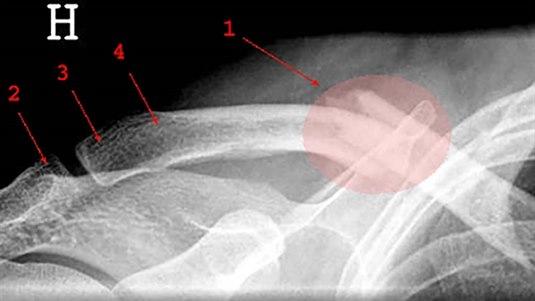

Kragebeinsbrudd forekommer hyppig, spesielt hos barn og unge. Over halvparten av bruddene skjer hos barn under 12 år. 80 prosent av bruddene sitter i midtre tredjedel, 15 prosent i ytre (distale) tredjedel og 5 prosent i indre (mediale) tredjedel. Kragebeinsbrudd kan oppstå som følge av direkte slag mot kragebeinet, støt mot skulderen fra siden, fallskader. Hos voksne kreves en større kraft for å brekke kragebeinet. Tilheling skjer langsommere hos voksne enn hos barn, og risikoen for komplikasjoner er større.

Kragebeinsbrudd behandles vanligvis uten operasjon med armen i fatle en kort periode (konservativ behandling). Indikasjon for operasjon er vanlig dersom beinet er blitt forkortet med mer enn 15 mm, eller at det er mer enn 15 mm avstand mellom bruddendene, eller at det foreligger et brudd med mer enn tre bruddstykker.

Feil sammenvoksning (malunion) av bruddendene - av ulike grader - kan oppstå hos opptil 2/3 av pasientene etter konservativ behandling, vanligvis er forkortning problemet. Manglende sammenvoksning (nonunion) eller dannelse av et falskt ledd (pseudartrose) kan også oppstå hos cirka 5 prosent av pasientene, enten de blir operert eller ikke. Operativ behandling gir eller bør gi korrekt stilling av bruddet etter inngrepet hos cirka 95 prosent.

Mulige komplikasjoner til inngrepet omfatter infeksjon (1-2 prosent), nerveskade (plexusskade), nonunion (5-10 prosent). Inngrepet utføres på avdelinger som ellers driver utstrakt operativ bruddbehandling. Operasjonen innebærer utskjæring av et beinstykke (osteotomi), korreksjon av feilstilling og festing av det nye bruddet med plater og skruer (osteosyntese).